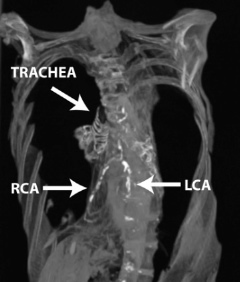

A CT scan of the princess was presented yesterday at the International Conference of Non-Invasive Cardiovascular Imaging in Amsterdam. The princess, who had blockages in her left and right coronary arteries, was one of 52 Egyptian mummies included in the study. Twenty of the mummies had definite signs of atherosclerosis, but only 3 had evidence of coronary narrowing.

(Photographs reprinted courtesy of Michael Miyamoto, MD)